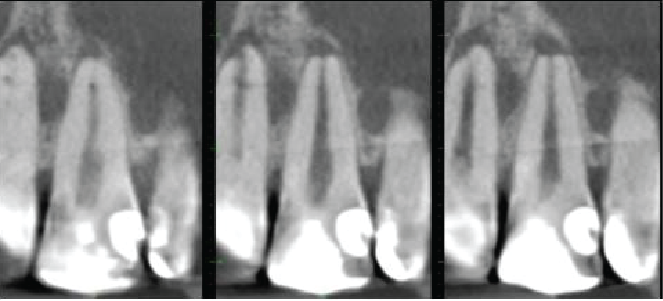

Cross sectional images of UL1

Mesio-distal

Labio-palatal

The UL1 has a very similar appearance to the UR1. The root canal is patent, with a lateral canal directed labially 2mm from the root apex. A periapical granuloma is extending down the labial side of the root, with a large fenestration of the labial cortical plate. There is apical inflammatory root resorption.